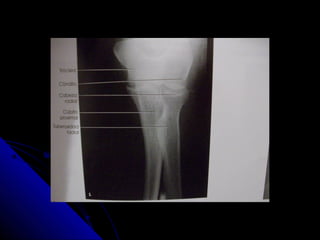

CODO. APCODO. AP

 Chassis 24 x 30 para las dosChassis 24 x 30 para las dos

proyecciones.proyecciones.

 Codo extendido y la mano en supinaciòn.Codo extendido y la mano en supinaciòn.

 R.C. perpendicular a la articulaciòn.R.C. perpendicular a la articulaciòn.

 Se ven: la cabeza, el cuello y laSe ven: la cabeza, el cuello y la

tuberosidad radiales ligeramentetuberosidad radiales ligeramente

superpuestos sobre el cùbito proximal.superpuestos sobre el cùbito proximal.

 Ausencia de rotaciòn de epicòndilo yAusencia de rotaciòn de epicòndilo y

epitroclea.epitroclea.

 En la proyección AP:En la proyección AP:

 el olècranon està oculto.el olècranon està oculto.

 El còndilo se articula con la cabeza radial ,El còndilo se articula con la cabeza radial ,

que es lateralque es lateral

 La tròclea se articula con el cùbito, que esLa tròclea se articula con el cùbito, que es

medial.medial.